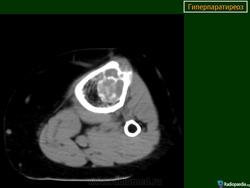

На КТ-изображениях пациента с почечной недостаточностью визуализируются множественные четко очерченные поражения остеолитического характера

Дифференциальный диагноз включает метастазы, множественную миелому и гиперпаратиреоз.

Биопсия выявила «коричневую» опухоль.